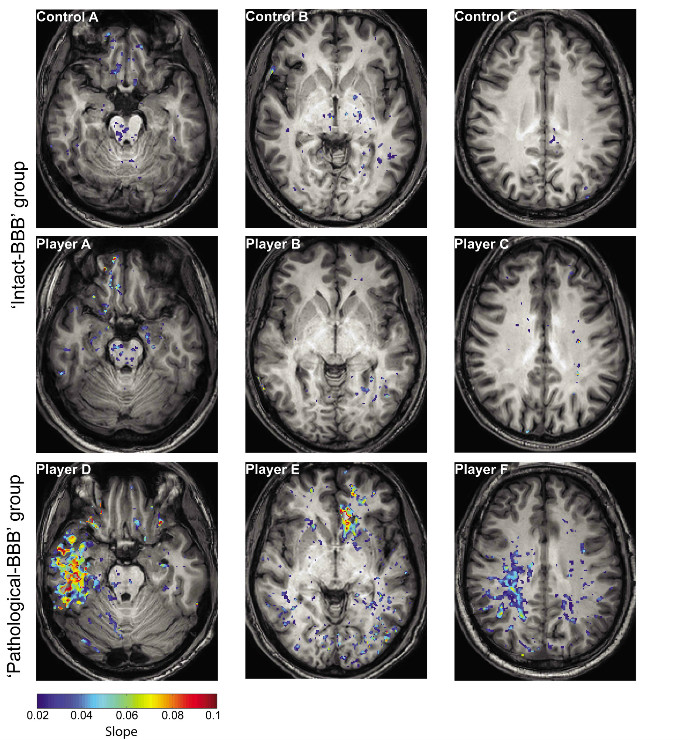

Israeli research team develops a special MRI procedure for visualizing damage to the blood-brain barrier.